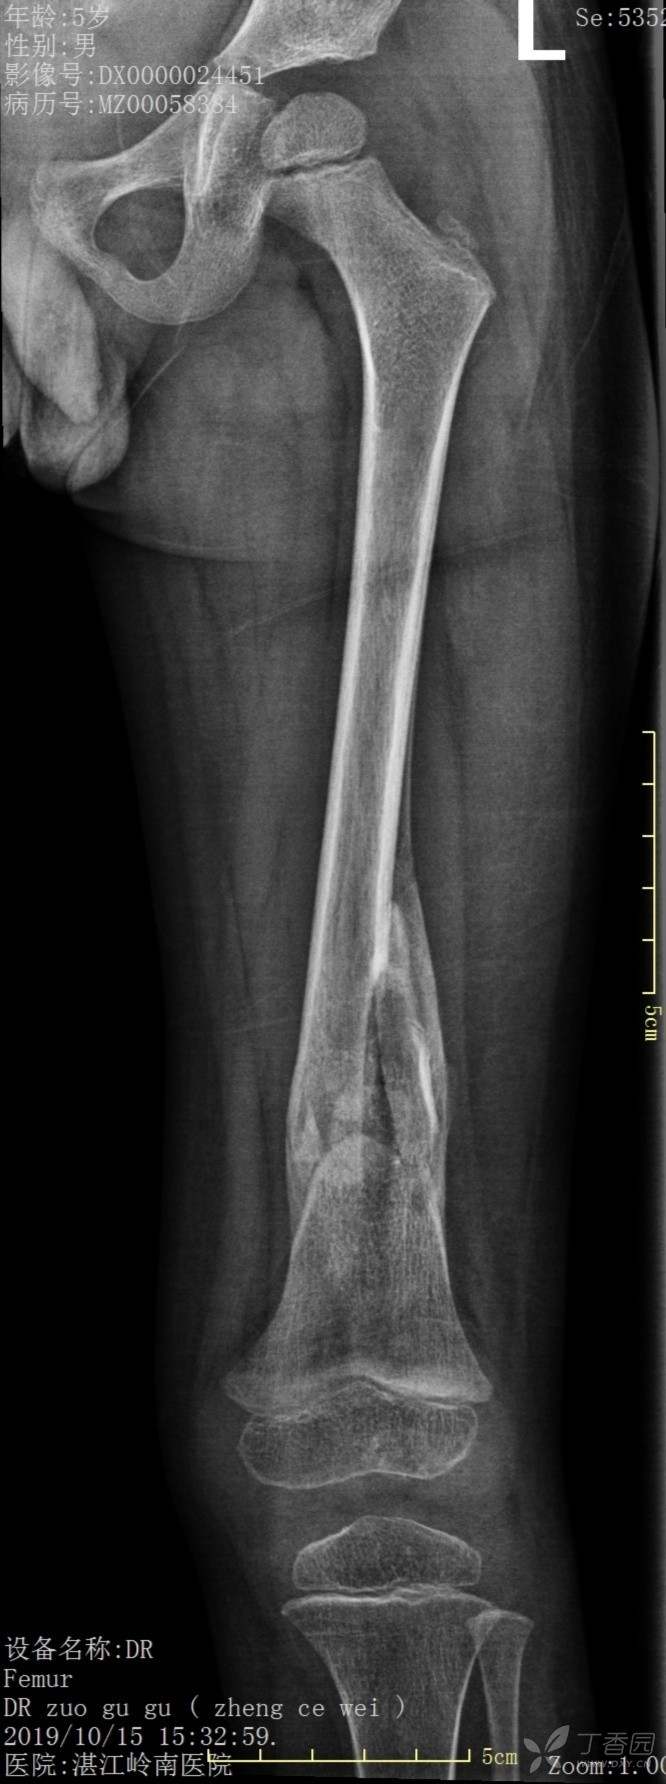

4岁患儿股骨骨折保守治疗一例

外伤时,保守1个月、2个月、6个月